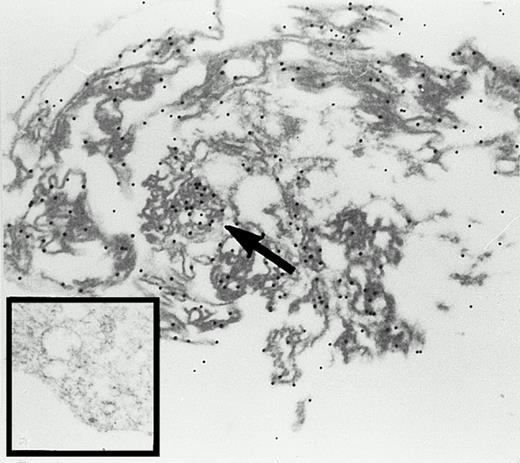

In rabbit reticulocytes the 15-LOX is expressed at a very high level. It has been estimated that 1 mL of packed cells contain about 4 mg of the enzyme.7 Recent cell fractionation studies suggested a membrane association of the enzyme in mature reticulocytes.25 We performed immunogold electron microscopy studies of rabbit reticulocytes (Fig3) and found that the enzyme is localized in the cytosol and at the cytoplasmic side of intracellular membranes. A strong 15-LOX labeling was consistently observed at the mitochondria (arrow). Because mammalian reticulocytes do not contain a nucleous, we could not check a hypothetical localization of the enzyme at the chromatin or at the nuclear envelope.

Immunogold labeling of the 15-lipoxygenase in rabbit reticulocytes. Cells were prepared and stained as described in the Materials and Methods section, 24,300-fold magnification. Inset, staining with a nonimmuno-IgG preparation; 27,100-fold magnification.